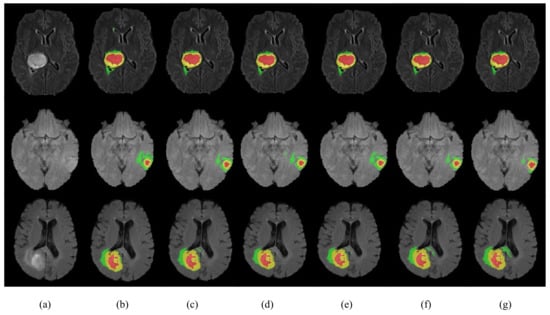

We conducted ablation experiments to evaluate the effectiveness of each module in HMNet on the BraTS 2020 dataset. The results of the ablation experiments are shown in Table 8 and Figure 9. We first used the shuffle block to replace the ordinary bottleneck block as Network 2 in Table 8, which reduced the network parameters by 86% and the computation by 30.2 G. The Dice coefficient of the ET was reduced by 1.1%, but the Dice coefficients of the WT and CT were 0.3% and 0.6% higher, respectively. Therefore, the shuffle block can guarantee no decrease in accuracy based on greatly reducing the network complexity. To evaluate the effectiveness of the LCC block, we used the LCC block to replace the shuffle block as Network 4 in Table 8, which further reduced the parameters and computation while improving the segmentation accuracy of ET, WT, and CT by 0.9%, 0.2%, and 0.2% due to the lightweight conditional channel weighting block we designed. From the segmentation results of Network 3 and Network 6, we can obtain that our LMRF module reduced the number of network parameters by about 1M, reduced the computational effort by about 3G, and made improvements in all three brain tumor regions to some extent. The Dice coefficients of our HMNet for the three brain tumor regions were 0.781, 0.901, and 0.823, respectively. The visualization of our segmentation results obtained using the network with different methods is given in Figure 9. The results of HMNet are closer to the ground truth and have better segmentation results than the baseline, which further proves the effectiveness of our improved method in our network.

Figure 9. Visualization of segmentation results. Each row represents a different sample. (a) is the modality of Flair. (bg) are the segmentation results of Network 1 to Network 5 in Table 8 and the ground truth. The yellow area is the enhancing tumor area. The red area is the necrosis and non-enhancing area. The green area is the edema area.